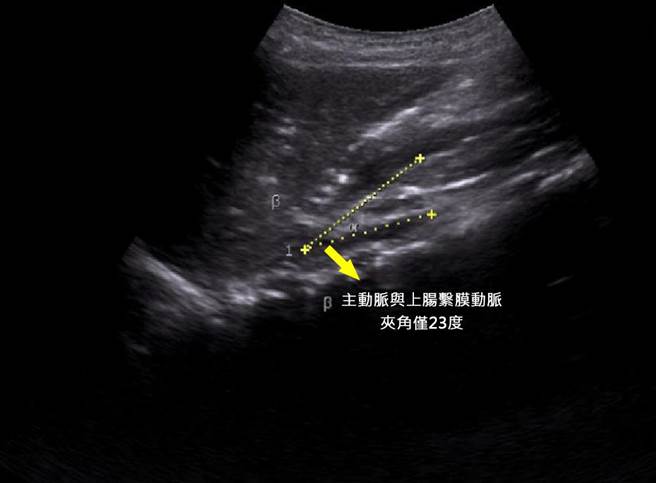

廖子涵表示,经超音波和电脑断层检查,发现该男孩的主动脉与上肠繫膜动脉之间夹角只有23度,这个夹角正常时大约38到65度之间。该情况的原因常见为体重过轻,上肠繫膜动脉缺少脂肪支撑,压迫到十二指肠,胃里消化的食物较难顺畅下到十二指肠,而导致食欲不振与频繁的噁心呕吐。